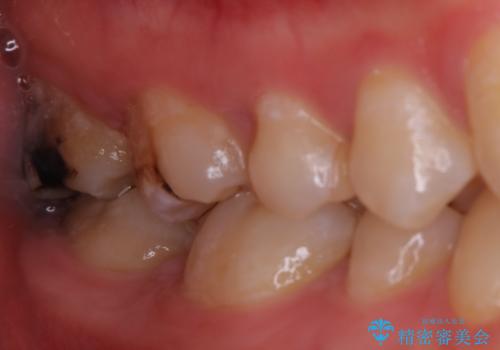

PGA(ゴールド)インレー 深い虫歯の治療